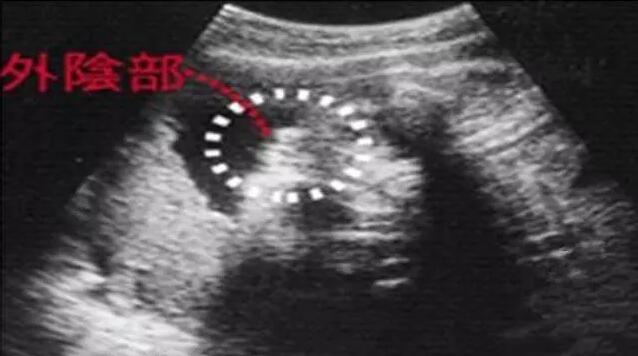

早期孕囊形状看男女

2022-11-24